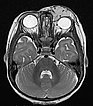

T2-weighted axial MRI with fat saturation. The mass medial to the left eye is relatively homogeneously hyperintense and sharply demarcated from the surrounding tissue. As a sign of strong arterial perfusion, some black, signal-free arterial vessels are seen in the lesion (“flow voids”). This is also typical of an infantile hemangioma.

T2-weighted axial MRI without fat saturation. The mass medial to the left eye is also relatively homogeneously hyperintense in this sequence and shows central flow voids. However, due to the lack of fat saturation, the mass is not as well demarcated from the surrounding adipose tissue.